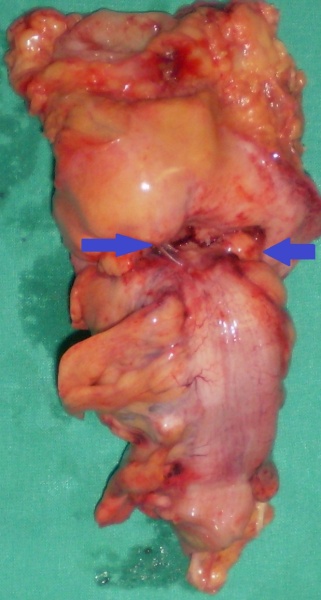

Εκτομαθέν τμήμα τελικής κολοστομίας. Μπλε βέλη — Θέσεις εκκολπώσεων (Ευγενική παραχώρηση Dr. V. Penopoulos)

Μη φλεγμαίνουσες εκκολπώσεις στο κολικό τμήμα αμέσως κάτω από την εξωτερικευμένη τελική κολοστομία (Ευγενική παραχώρηση Dr. V. Penopoulos)